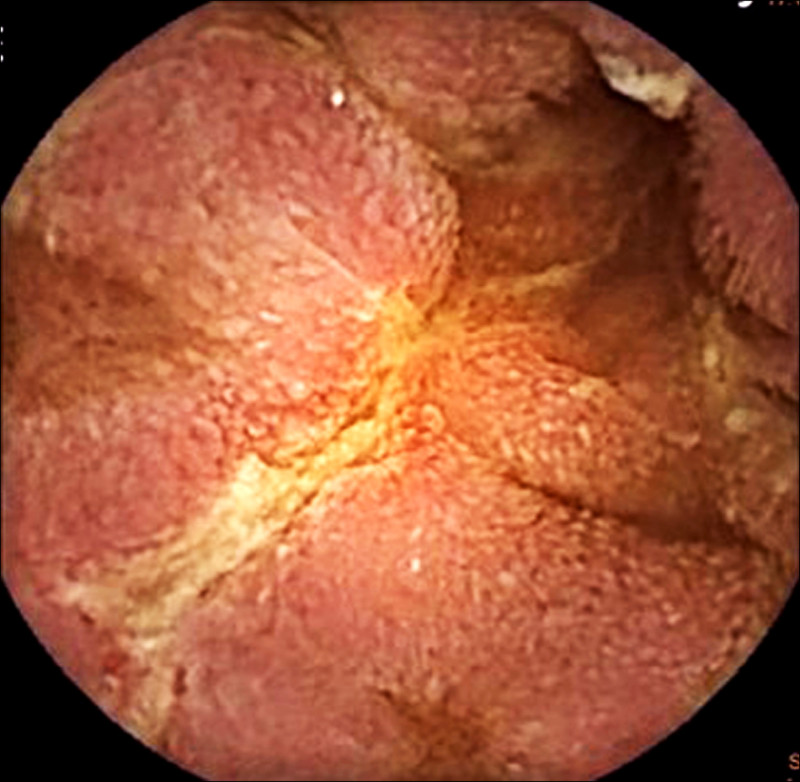

章振旺說,這名男性業務員經膠囊內視鏡檢查,結果顯示,小腸從空腸到迴腸多處可見跳躍式病灶及縱向潰瘍,經影像與病理檢查綜合判讀,確認為克隆氏症,在接受類固醇與免疫調節藥物治療後,病情已大幅穩定,體重也不再下降。

章振旺指出,小腸疾病較難以利用傳統腸鏡檢查一窺全貌,膠囊內視鏡正好補足盲點,對克隆氏症早期發現與評估病灶嚴重程度有極大幫助。